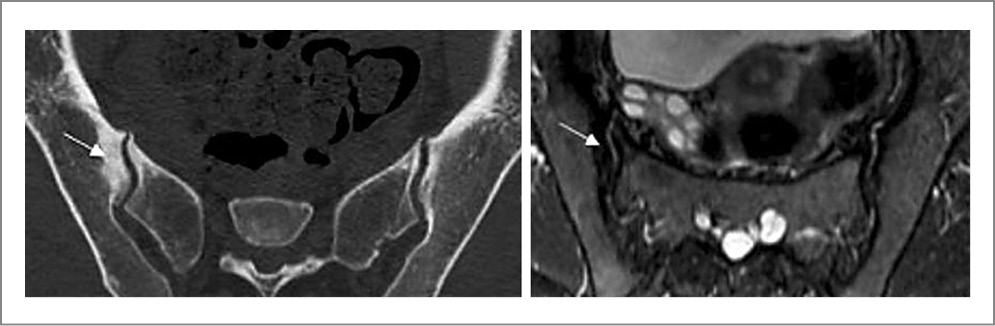

Пациентка В. 29 лет направлена на консультацию в 2023 г. с подозрением на АС. Жалобы на боли в нижней части спины и ягодиц, которые впервые остро возникли на 9-м месяце беременности (за 4 года до настоящей консультации), были стойкими и очень интенсивными. По результатам МРТ (рис. 1) сделано заключение о наличии сакроилиита. После родов боли продолжались, но постепенно стали менее сильными и непостоянными. Скорость оседания эритроцитов и уровень СРБ не повышались. Обнаружен HLA-B27. Установлен диагноз АС. Во время осмотра пациентки осанка существенно не нарушена, движения в позвоночном столбе не ограничены и безболезненны, болезненность при пальпации гребня левой подвздошной кости и в проекции левого КПС. Пересмотр МРТ четырехлетней давности позволил обнаружить стресс-переломы крестца с обеих сторон и массивный отек костного мозга вокруг линий переломов. Повторное МРТ-исследование (2023 г.) показало, что отек костного мозга в крестце отсутствует. На рентгеновском снимке признаков сакроилиита, нарушений целостности крестца не найдено. Рентгеноостеоденситометрия: показатели минеральной костной плотности в поясничном отделе позвоночника и проксимальном отделе бедренной кости в норме. Предположение об АС отвергнуто, установлен диагноз заживших (заживающих?) стресс-переломов крестца.

Рис. 1. Пациентка В. 29 лет. Стресс-переломы крестца, развившиеся на 9-м мес беременности. МРТ (коронарная проекция, режим STIR): в обеих боковых массах крестца отмечаются обширные зоны сигнала повышенной интенсивности (отек костного мозга), на фоне которого прослеживаются линии переломов (указаны стрелками).